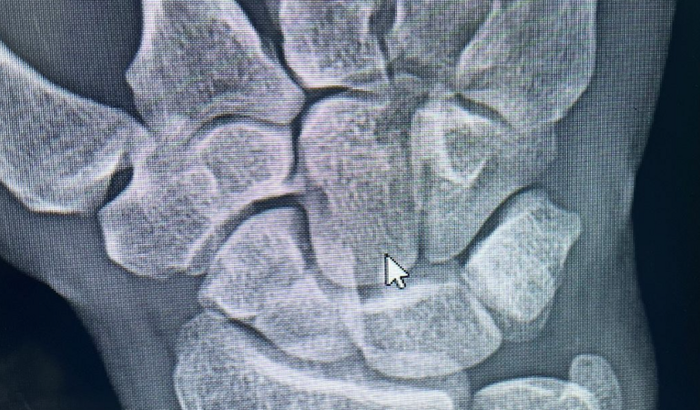

Galera, como a maioria já sabe, tive uma fratura seríssima no escafóide e pulso. Infelizmente vou precisar operar e o SUS não cobre o meu tratamento. Estou pedindo ajuda a vcs, pois vou precisar operar com urgencia! A minha dor é muito grande, vou precisar de pinos e uma recuperação difícil.